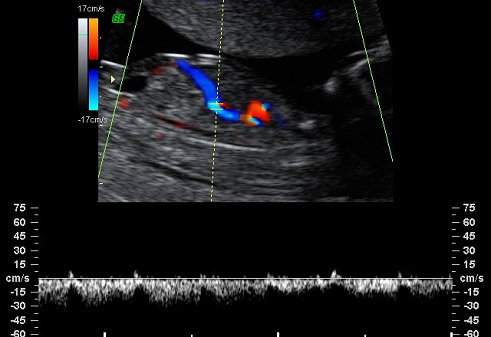

Feto de 12 semanas con medición del ductos venoso

El ductos venoso es la comunicación entre la vena umbilical y el corazón y en esta imagen vemos el corte longitudinal en un feto de 12 semanas. Se trata de un marcador ecográfico de aneuplodía (anomalía cromosómica) en la semana 12 de embarazo, ya que un 80% de los fetos con trisomía 21 (síndrome de Down) tienen un flujo anormal en el ductos venoso.

Esta ecografía debe realizarse en un hospital o centro con ecografistas expertos. Si aparece alguno de estos tres marcadores, el riesgo pasa de ser intermedio a alto y se aconsejará una prueba invasiva. Si no hay ninguno de estos tres marcadores, el riesgo pasará a ser bajo y no se aconsejará ninguna otra prueba diagnóstica.